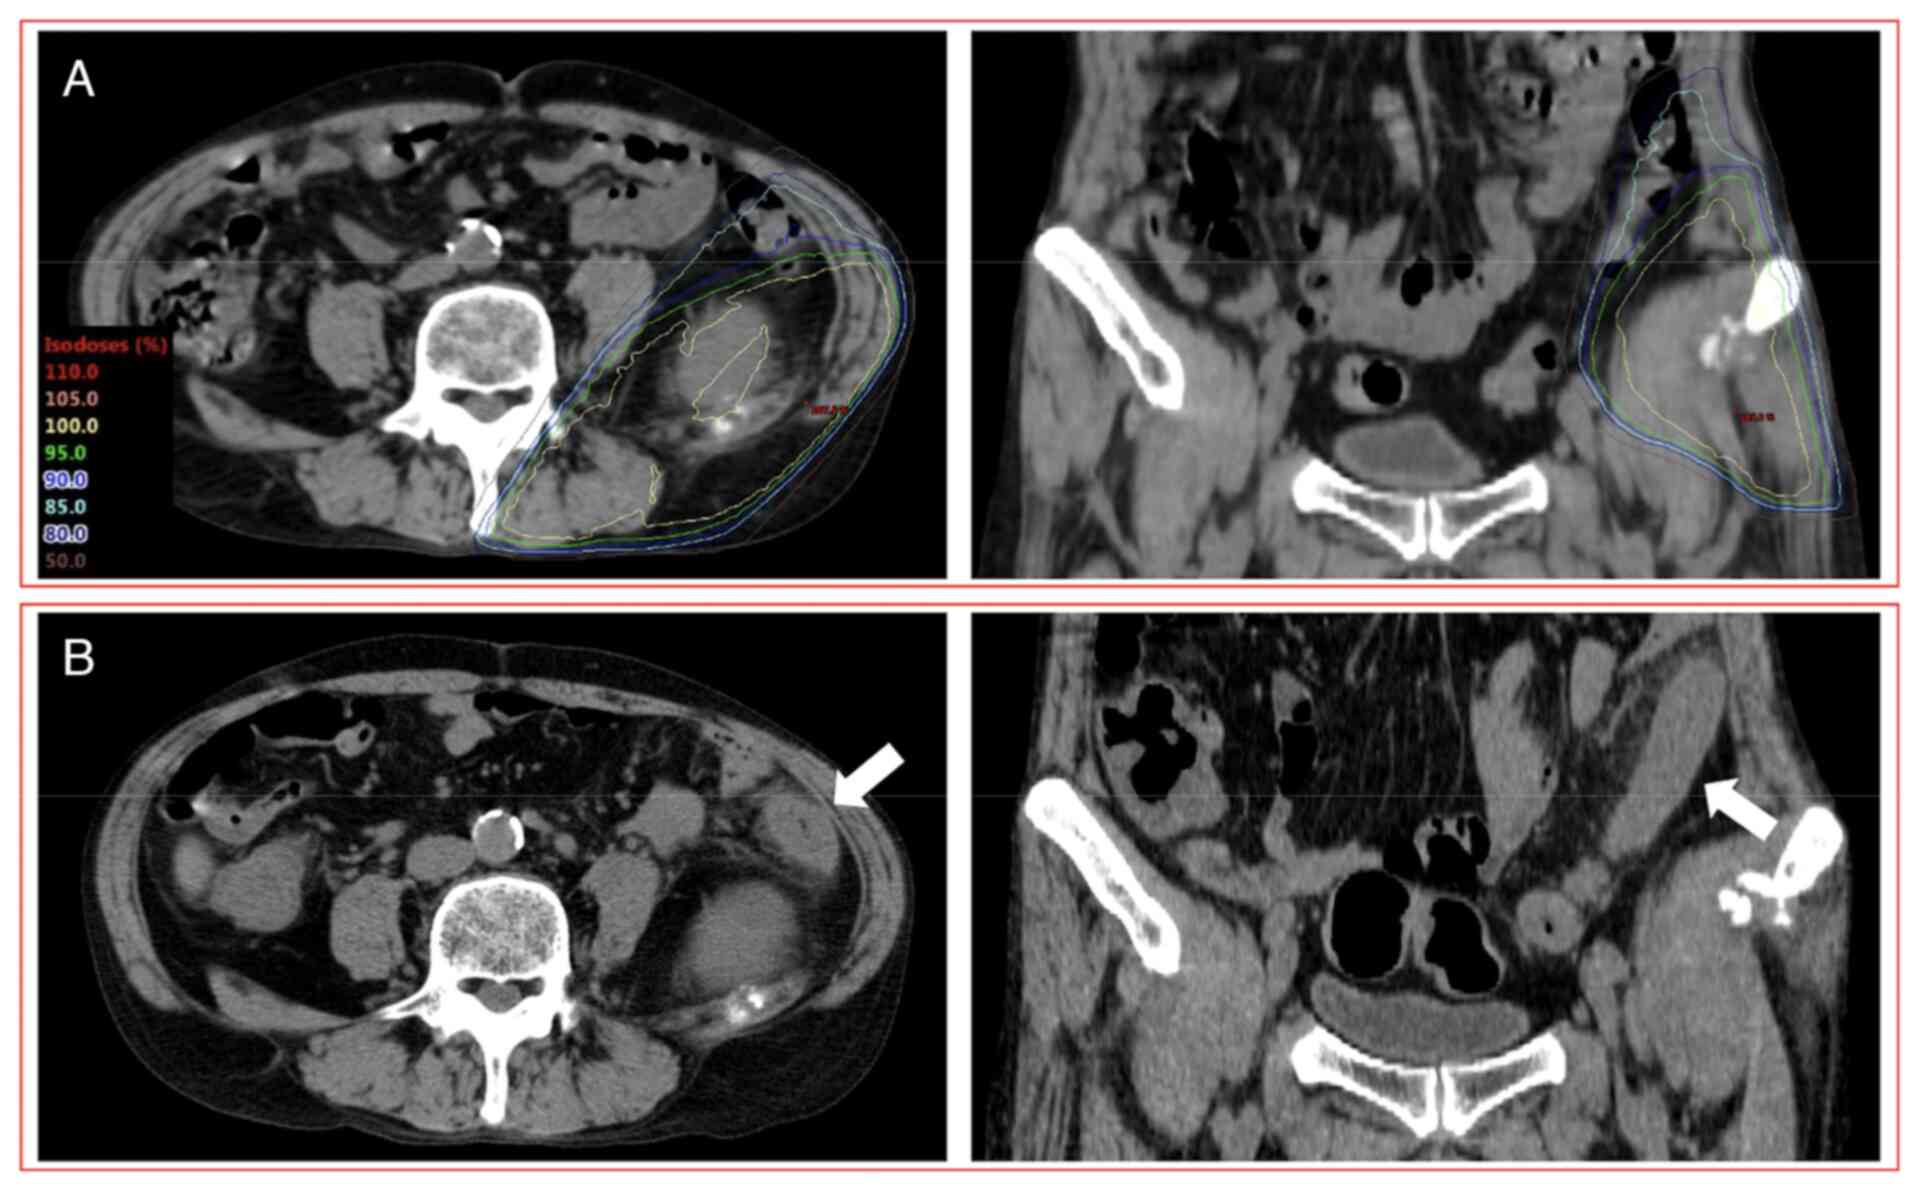

Figure 3

A patient (58 years, male) with grade 2 RIE after PRT involving the large bowel and administration of ICIs. (A) CT images indicating the dose distribution of PRT to an iliac bone metastasis (28.8 Gy in 8 fractions). (B) CT images acquired 17 days after the completion of PRT. This patient developed grade 2 RIE with segmental and circumferential bowel wall thickening and pericolic fat stranding in the area of the irradiated field (white arrow) as observed in CT images after combination therapy with PRT and ICIs. Left panel showed transverse images and the right panel showed coronal images. RIE, radiation-induced enterocolitis; PRT, palliative radiotherapy; ICIs, immune checkpoint inhibitors; CT, computed tomography.

Another patient (58 years, male) who had grade 2 RIE was administered anti-PD-1 (nivolumab) plus anti-CTLA-4 (ipilimumab) combination therapy with chemotherapy (carboplatin and pemetrexed) 6 days after the completion of PRT (8x3.6 Gy) (Fig. 3). This patient had diarrhea and abdominal pain 7 days after the completion of PRT. CT images acquired 17 days after the completion of PRT revealed findings of enterocolitis limited to the irradiated field. Biopsy was not performed. The dose-volume parameters of D2cc, V10 and V20 of the large bowel were 26.9 Gy, 67.2 cc and 38.4 cc, respectively.